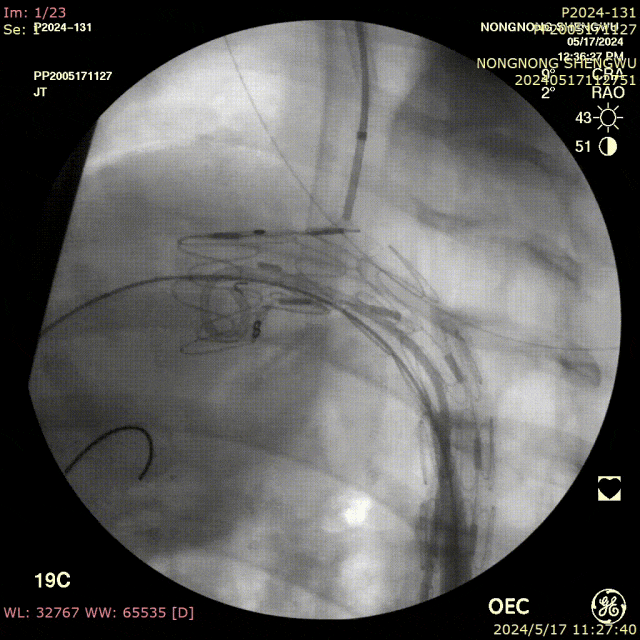

我们在两头35kg巴马公猪中完成动物实验:

成功实现弓上分支的快速、准确原位开窗;

破膜过程流畅,无分支或主动脉损伤;

取出标本可见圆形破口、支架贴合良好,证实技术可行性。

动物实验

巴马公猪35kg